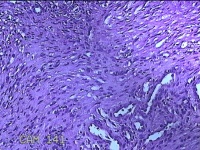

宫腔粘连带

性别

女

年龄

44岁

临床诊断

稽留流产 宫颈炎 宫腔粘连? 宫颈息肉

一般病史

停经1月,发现胚胎停育半天。

标本名称

大体所见

灰白暗红色不规则碎组织1.3x1.2x0.3cm一堆。